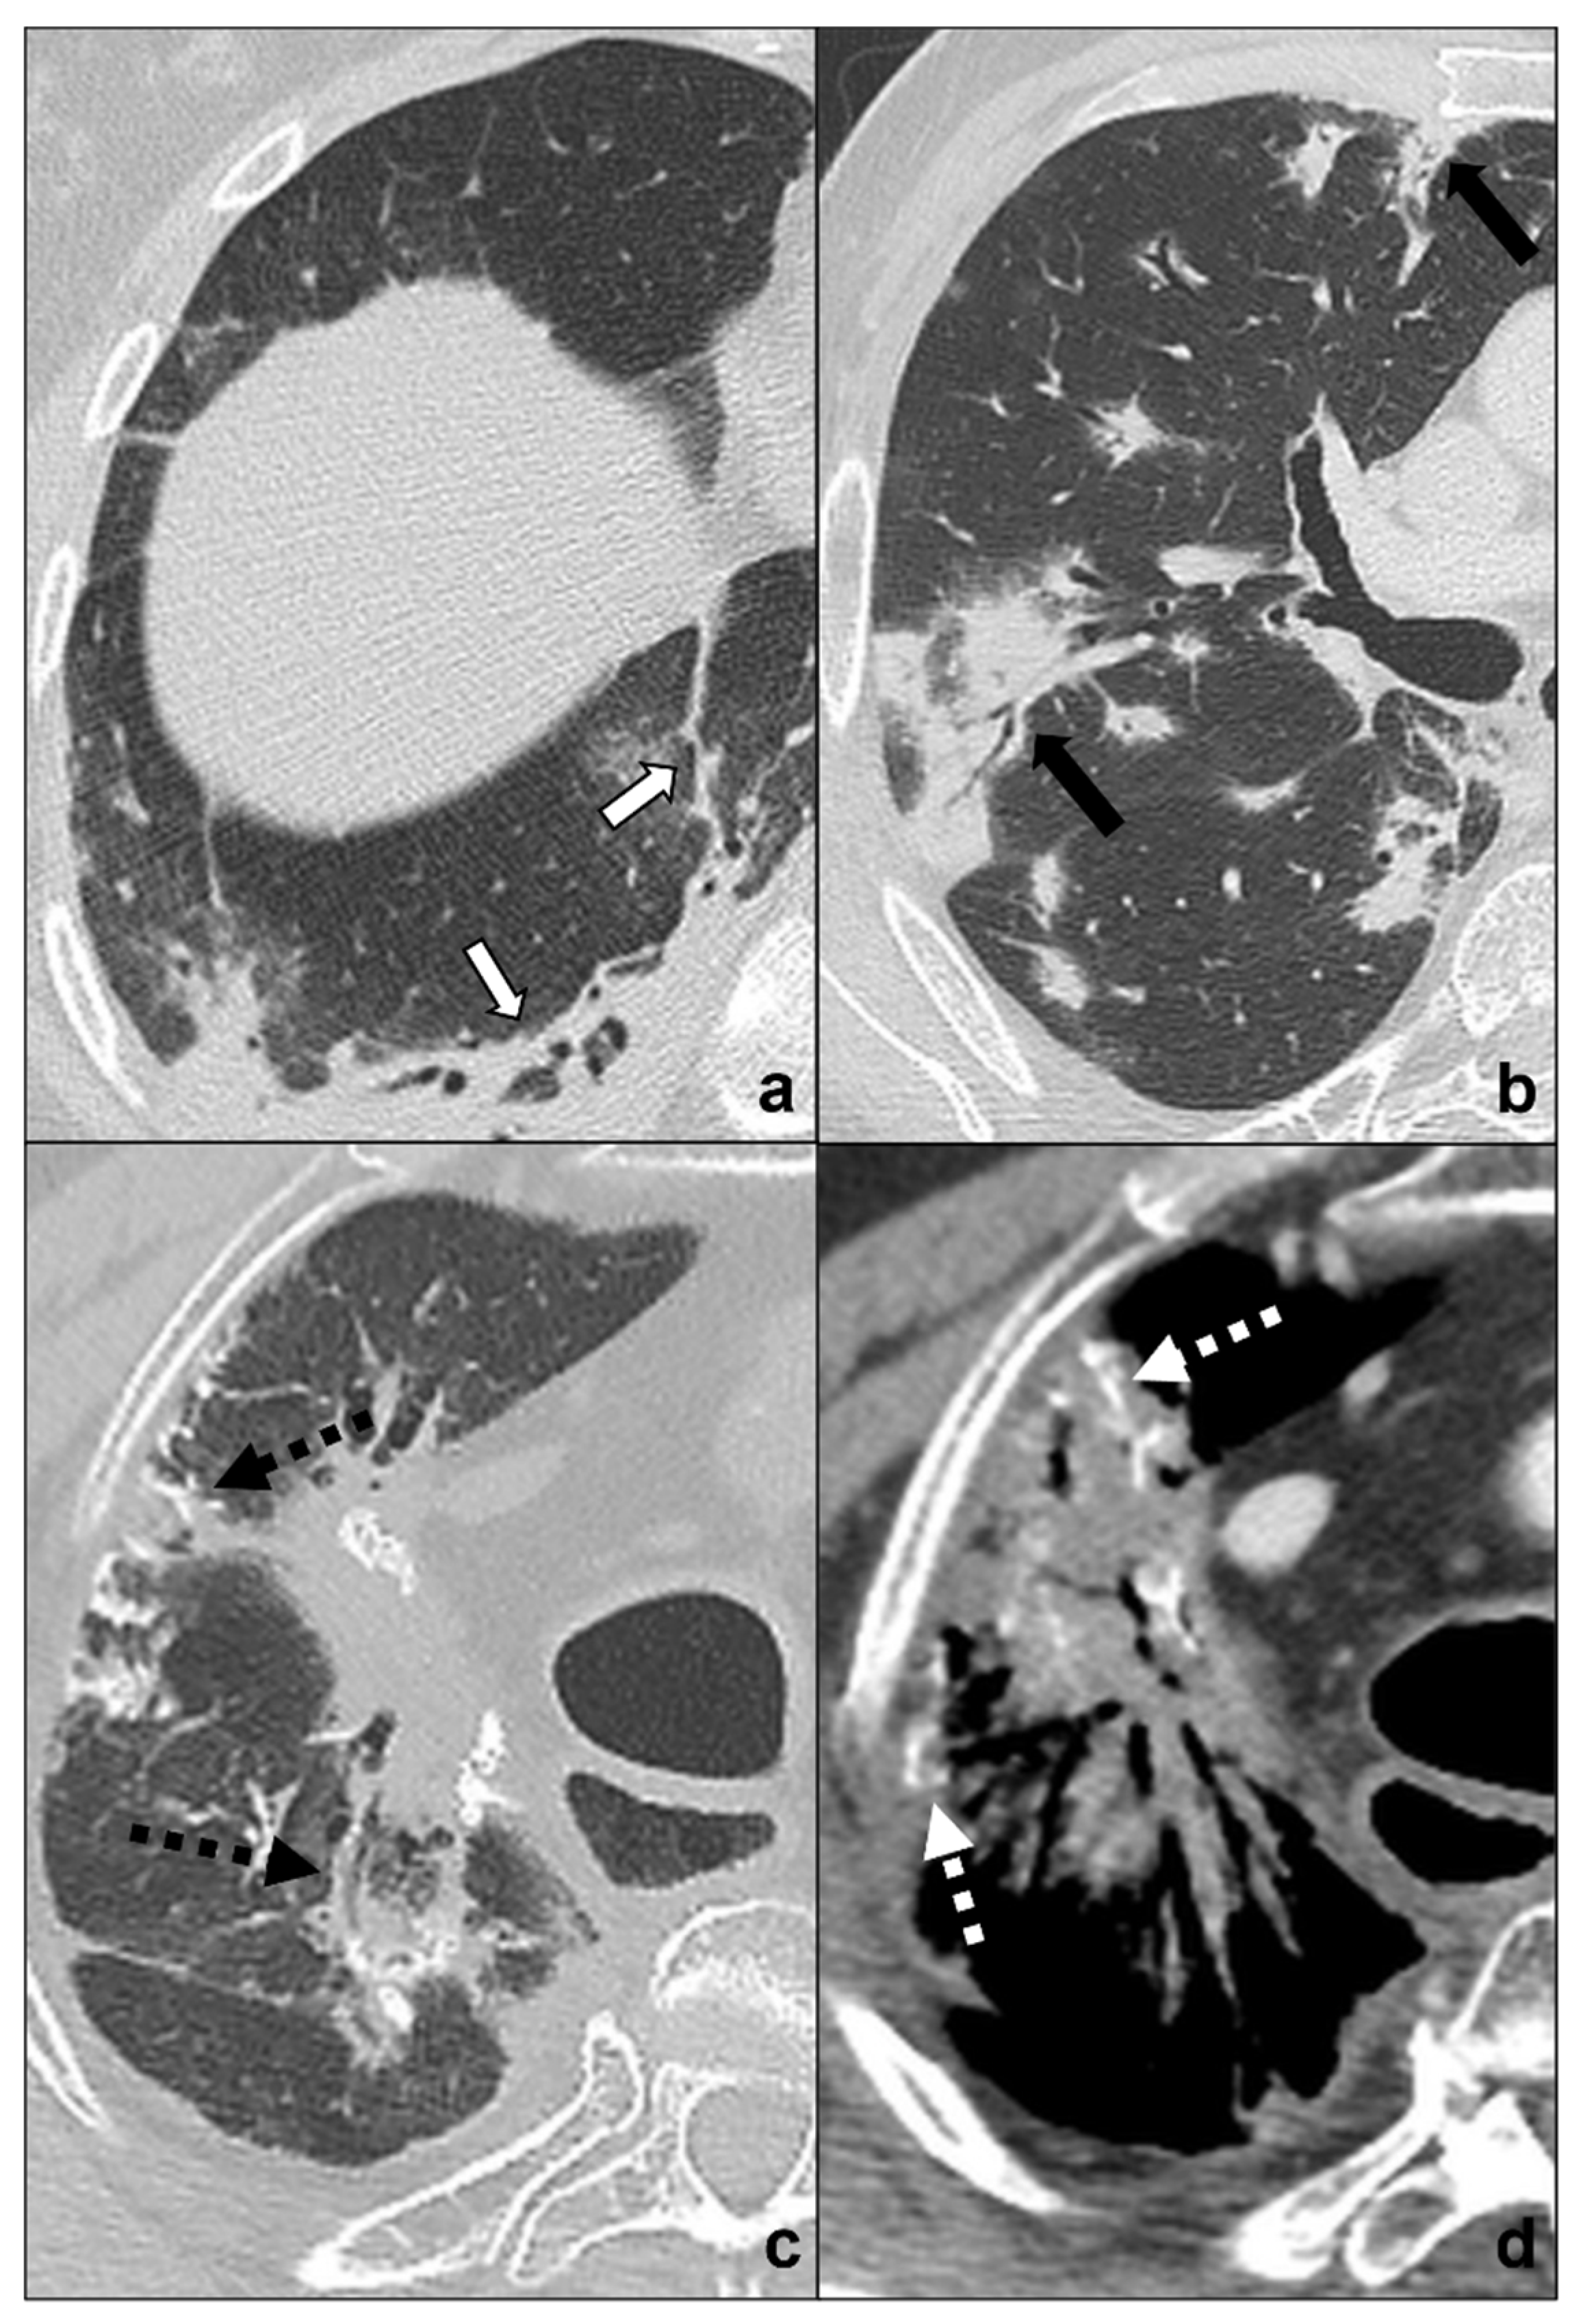

Figure 6.

(a–d) Chest CTs showing differential diagnoses of COVID-19 pneumonia stage 4/absorption phase characterized by parenchymal bands (black-bordered white arrows in (a). Differential diagnoses generally include chemotherapy-induced lung disease (b) and radiation-induced lung disease (c,d). In (b), HRTC of a patient presenting with OP showing pulmonary parenchymal ill-defined bands and consolidations during a chemotherapy cycle (black arrows in (b)); in (c,d), chest CT of a patient who underwent radiotherapy for an apical lung cancer, showing an extensive mass with irregular margins, pleural and mediastinal retraction striae (black dotted arrow) and with some calcification within (dotted white arrows) in the field of radiation. Lungs: mean window with 1500 HU; mean window level −600. Mediastinum: mean window with 350 HU; mean window level 50 HU.

Although COVID-19 pneumonia may be an incidental diagnosis in asymptomatic patients [15], acute symptoms worsening and changing should always suggest an overlapping pathology or a progression and require urgent investigation (Figure 7a–d).

Figure 7.

(a–d) Chest CT of an oncologic patient affected by a paramediastinal lung cancer located in the apical segment of the right upper lobe (dotted white arrow) and undergoing chemotherapy and radiotherapy. After admission to the first aid with ageusia, anosmia, and fever, a chest CT scan was performed showing subpleural areas of ground-glass (white arrow in (b)) and crazy paving (black arrow in (c)) with the typical reversed halo sign or atoll sign (dotted black arrow in (d)), parenchymal consolidations (black circle in (a)) and subpleural parenchymal bands together with crazy paving opacities (black-bordered white arrow in (d)). Lungs: mean window with 1500 HU; mean window level −600. Mediastinum: mean window with 350 HU; mean window level 50 HU.